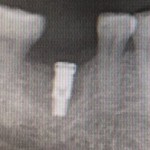

右下6番が保存不可能だったため、残念ながら抜歯となり、数ヶ月ほど経過。

インプラント治療を希望され、同時に骨造成も行いました。